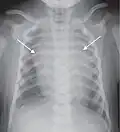

Mediastinal structures on a chest radiograph.

In the average person, the diaphragm should be intersected by the 5th to 7th anterior ribs at the mid-clavicular line, and 9 to 10 posterior ribs should be viewable on a normal PA inspiratory film. An increase in the number of viewable ribs implies hyperinflation, as can occur, for example, with obstructive lung disease or foreign body aspiration. A decrease implies hypoventilation, as can occur with restrictive lung disease, pleural effusions or atelectasis. Underexpansion can also cause interstitial markings due to parenchymal crowding, which can mimic the appearance of interstitial lung disease. Enlargement of the right descending pulmonary artery can indirectly reflect changes of pulmonary hypertension, with a size greater than 16 mm abnormal in men and 15 mm in women.[6]

Appropriate penetration of the film can be assessed by faint visualization of the thoracic spines and lung markings behind the heart. The right diaphragm is usually higher than the left, with the liver being situated beneath it in the abdomen. The minor fissure can sometimes be seen on the right as a thin horizontal line at the level of the fifth or sixth rib. Splaying of the carina can also suggest a tumor or process in the middle mediastinum or enlargement of the left atrium, with a normal angle of approximately 60 degrees. The right paratracheal stripe is also important to assess, as it can reflect a process in the posterior mediastinum, in particular the spine or paraspinal soft tissues; normally it should measure 3 mm or less. The left paratracheal stripe is more variable and only seen in 25% of normal patients on posteroanterior views.[7]